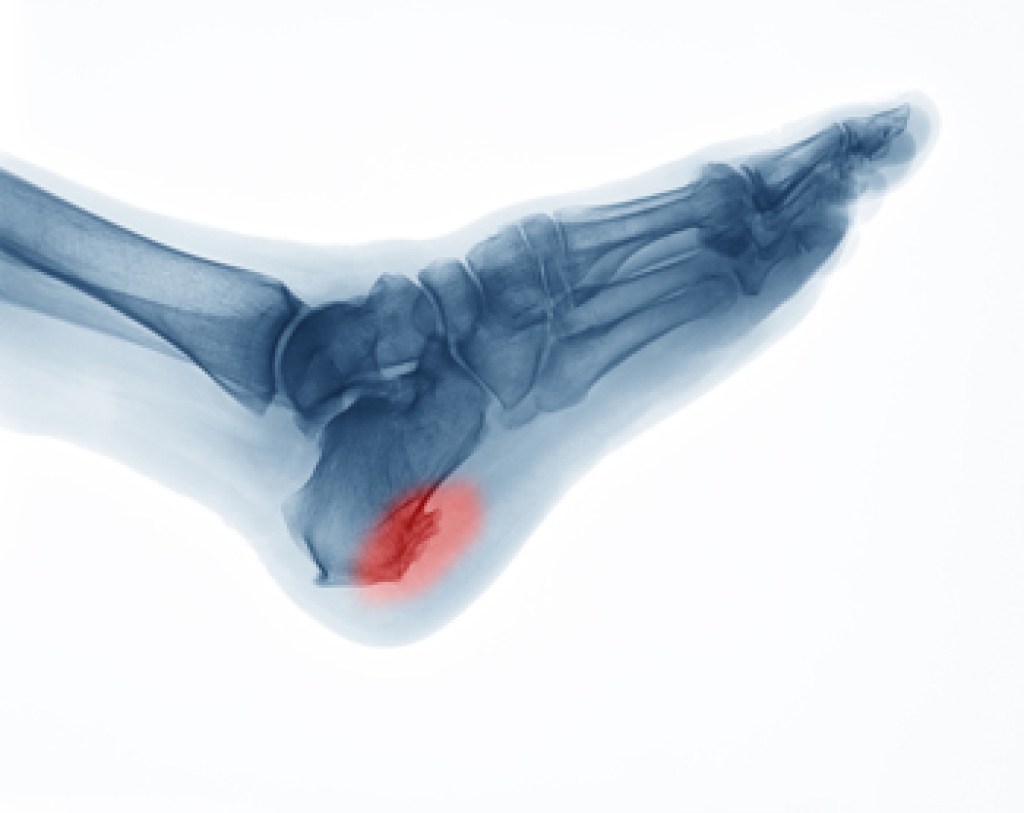

A heel spur can produce severe pain and discomfort, despite their small size. It is defined as a bony growth that forms on the bottom of the heel, generally as a result of consistent pressure the heel endures. Pain that often accompanies this condition is caused by an inflamed ligament that connects the heel to the toes, causing difficulty in completing daily tasks. This can happen from being obese, frequently running, or possibly from wearing shoes that do not fit correctly. Larger heel spurs may feel like a small hook on the inside of the heel that can be an inch or longer. Intense heel pain will often bring the patient to a podiatrist to have an X-ray taken, which can determine the exact size of it, although the pain is typically caused by inflammation. At the first sign of heel pain, it is strongly urged that you speak with a podiatrist who can offer treatment methods that are correct for you, which may include surgery for removal.

Heel spurs are formed by calcium deposits on the back of the foot where the heel is. This can also be caused by small fragments of bone breaking off one section of the foot, attaching onto the back of the foot. Heel spurs can also be bone growth on the back of the foot and may grow in the direction of the arch of the foot.